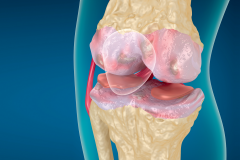

Polecamy też teksty poruszające klasyczne zagadnienia, jednak prezentujące nowe lub rozszerzone podejście do typowych problemów pacjentów. Należą do nich dolegliwości odcinka szyjnego, nerek, zmiany zwyrodnieniowe stawów kolanowych, a także dysfunkcja mięśni dna miednicy.